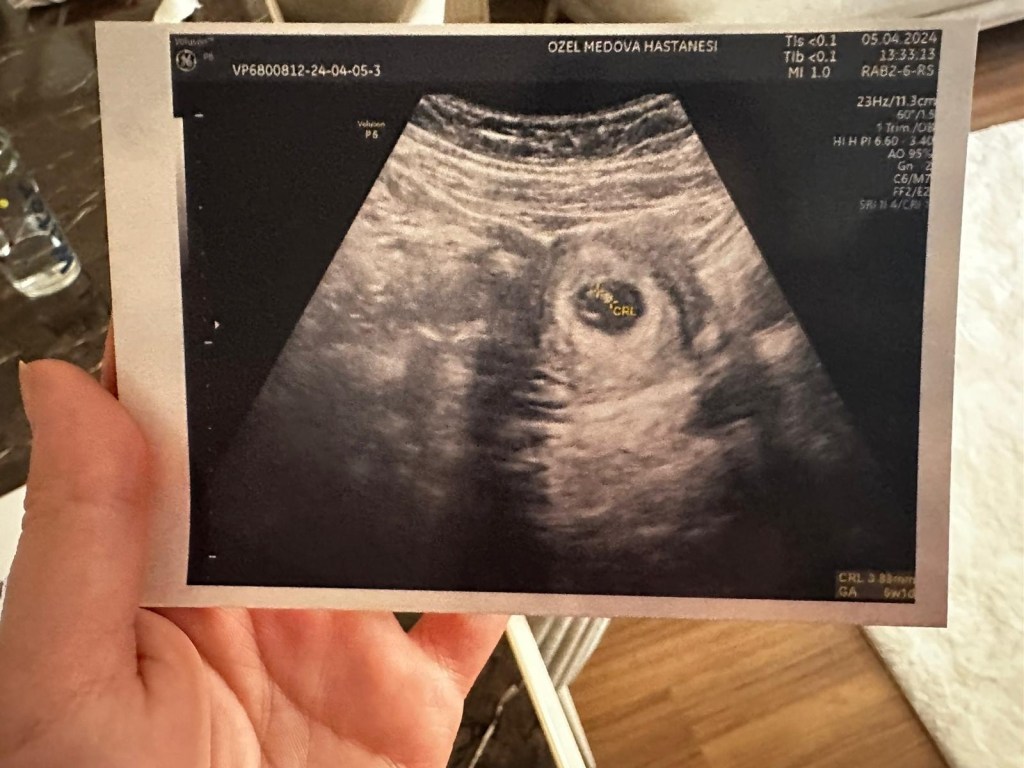

Çok farklı bi duygu, tarifsiz… saat 05.00 uyandık kahvaltı ardından hastaneye geçtik. Doktorumuzla normal doğum diye konuştuk. Tüm gün egzersiz çömelme yürüyüş ile geçti. 12 saat ardından 6 cm olduğu halde o koca kafan :)) kanala inmediği için sezeryana geçtik. Korkuluydum haliyle çok ağladım 🙂 sezeryana girdik senin sesini duydum 🙂 yanıma getirdiler ve ilk fotoğrafımız yavrum benim hayatımıza girdin. Linam❤️